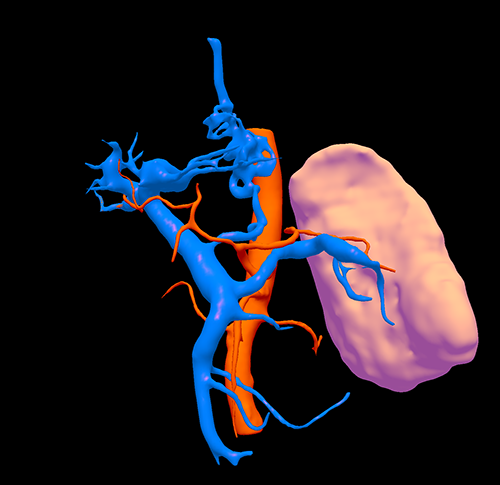

门脉高压、右肝动脉门静脉瘘、胆囊结石----脾切除、贲门周围血管离断、肝右动脉结扎、胆囊切除